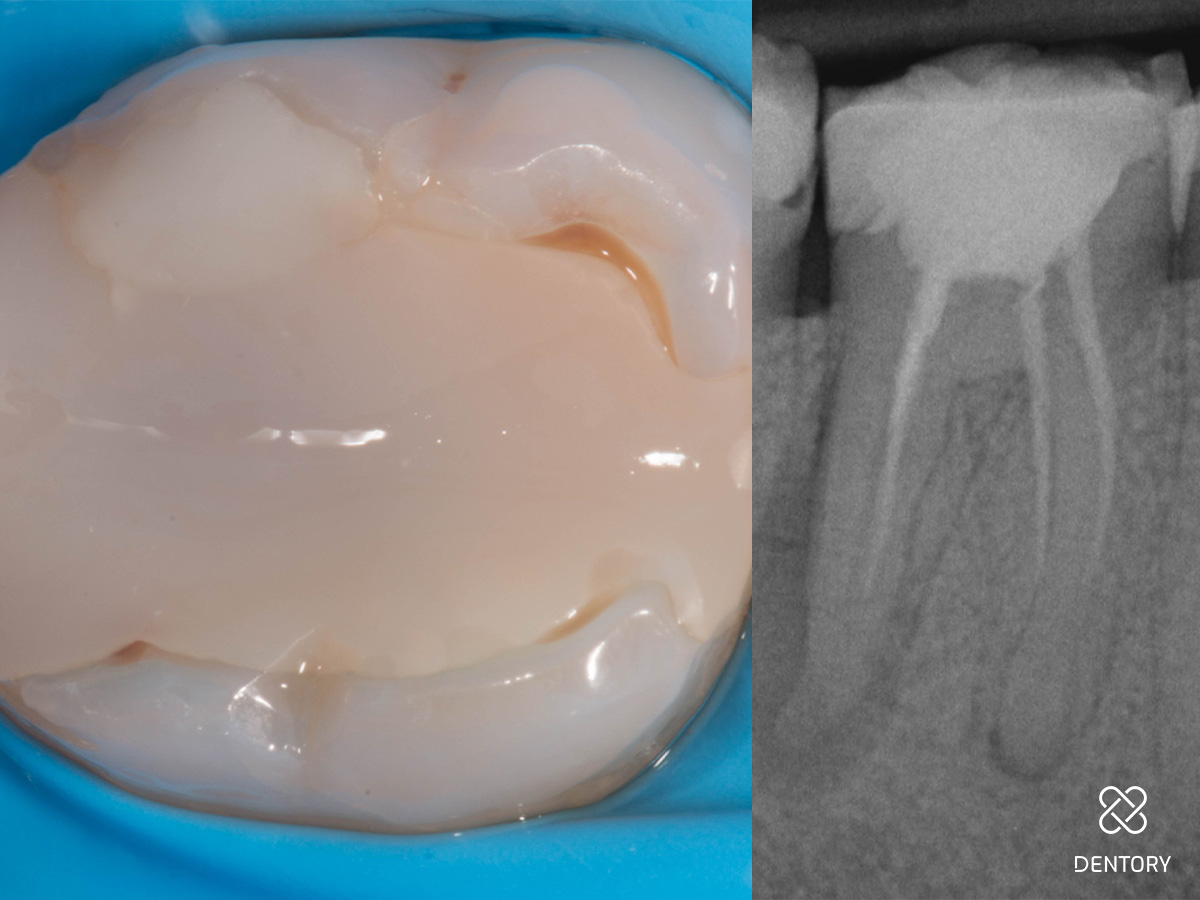

Abbildung 3

Initiale Zugangskavität: Mit einem Rosenbohrer wurde die alte Guttapercha reduziert. Für den Prä-Endo Aufbau wurden sowohl mesial als auch distal die Höcker partiell eingekürzt. Dies senkt das Frakturisiko bis zur indirekten Post-Endo Restauration.

Abbildung 4

Darstellung der partiellen Höckerreduktion von bukkal. Einkürzung um ungefähr 1,2 mm.